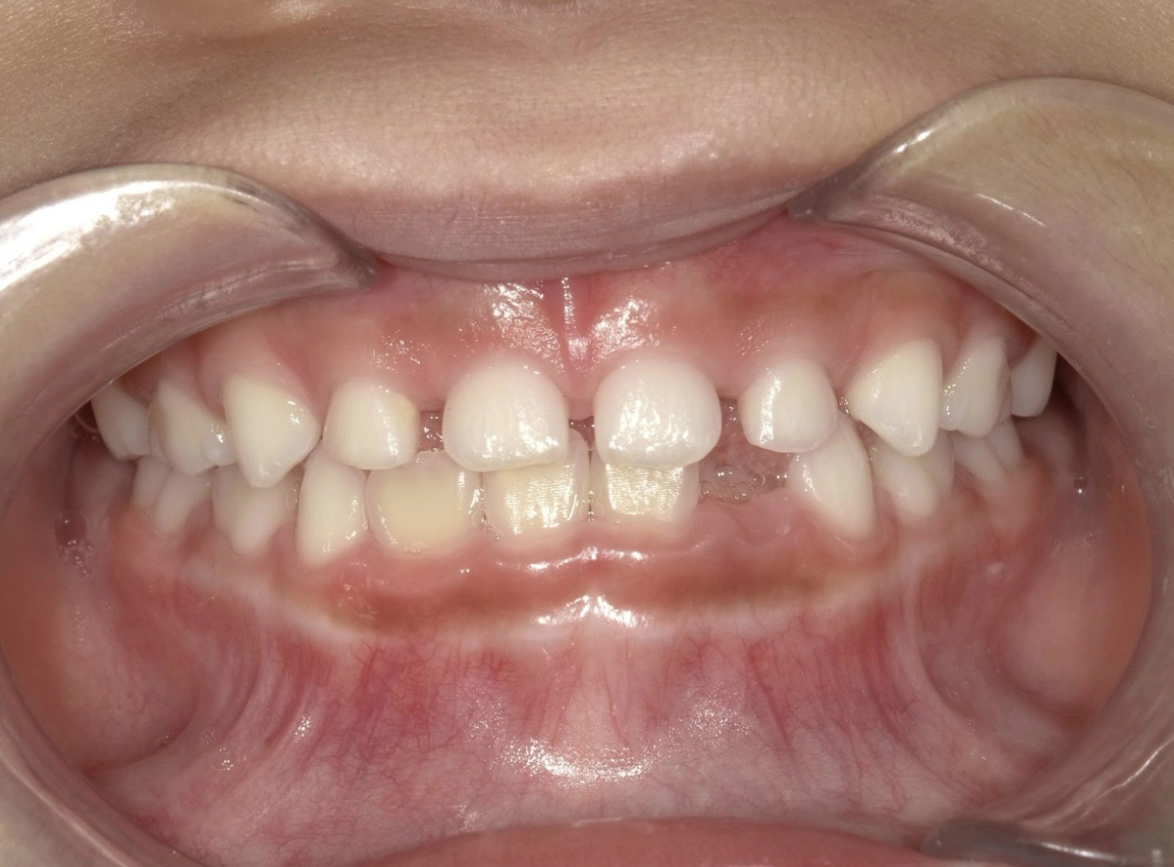

治療前

治療後

| 術名 | 小児矯正の症例 |

|---|---|

| 年齢 | 12歳 |

| 性別 | 女児 |

| 主訴 | 前歯の凹凸 |

| 診断名 | 下顎前突・叢生 |

| 治療内容 | 顎顔面矯正 |

| 治療期間 | 26ヶ月 |

| 費用 | 50万+税 ※別途月々の調整料(5500円)がかかります |

| リスク・副作用 | 疼痛・咬合違和感、等 |